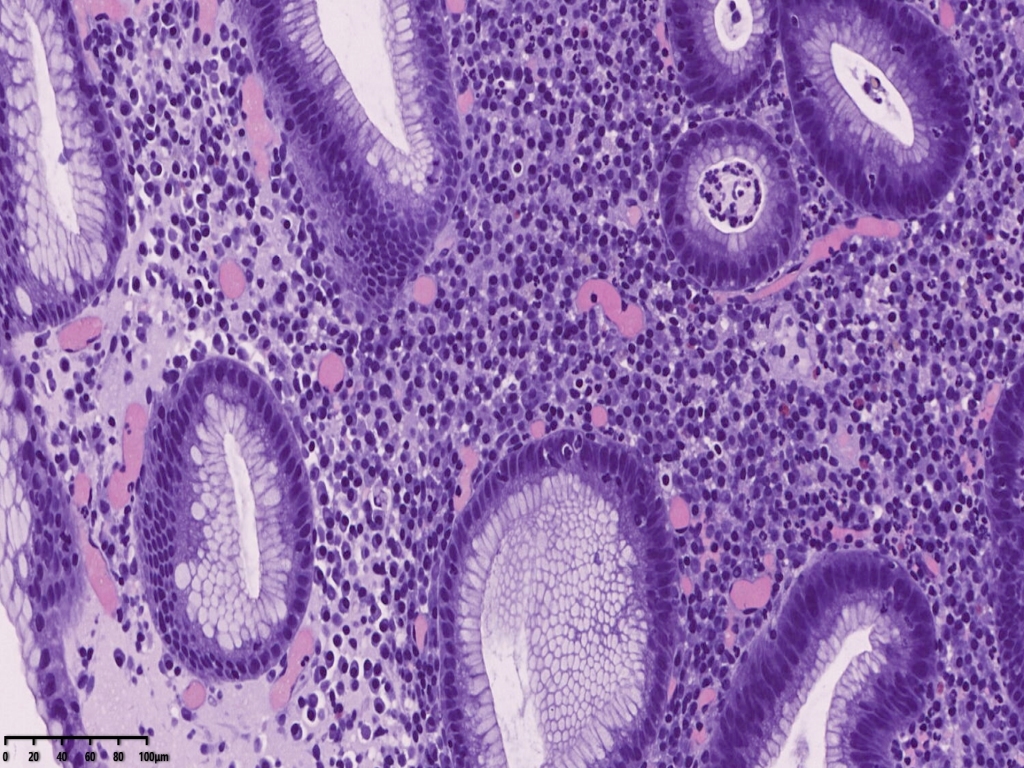

免疫组化常规片内异型上皮细胞更显著。核偏位的异型上皮细胞,胞浆似泡沫样,但是与组织细胞不同,组织细胞核位于中央,与印戒细胞也不太一样,印戒细胞胞浆内为明显的粘液空泡。